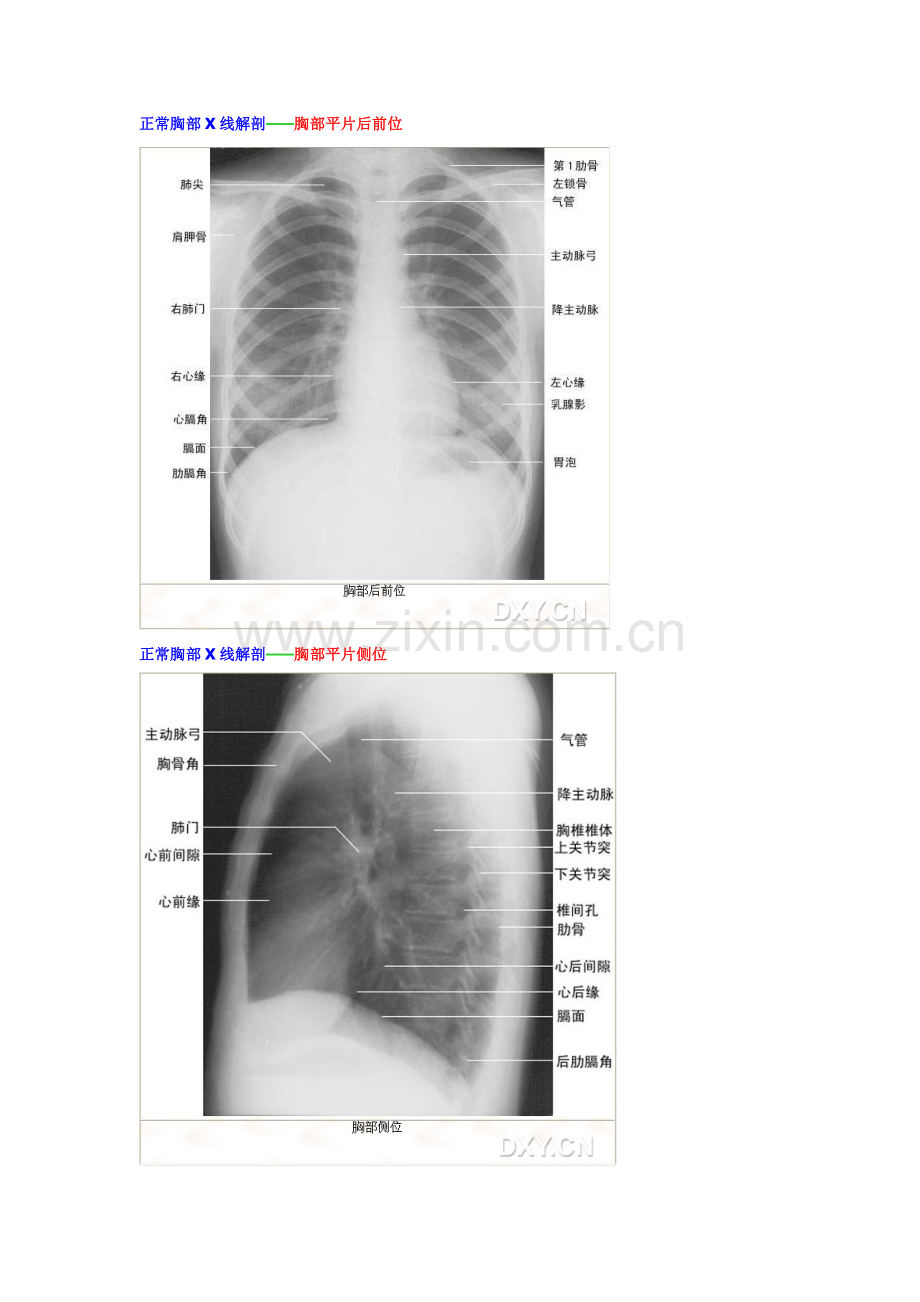

X线正常解剖(基础+精华) 正常头颅X线解剖——头颅平片后前位 正常头颅X线解剖——头颅平片侧位 正常胸部X线解剖——胸部平片后前位 正常胸部X线解剖——胸部平片侧位 正位胸片10大观察死角及影像观片原则 1、颈部:颈部软组织肿块(如甲状腺肿块); 2、肺尖、第1肋骨:如肺上沟癌,第1肋骨骨折、破坏等,要注意两侧对比; 3、锁骨胸骨端、胸锁关节、胸骨:锁骨胸骨端骨质破坏,胸锁关节半脱位,胸骨骨折等; 4、锁骨尖峰端、锁骨外1/3:此处骨折或骨质破坏易漏诊; 5、肩胛骨:骨折或骨质破坏易漏诊; 6、肋骨腋缘、前肋:无错位骨折易漏诊,肋骨腋缘胸膜反应就是提示骨折得重要征象; 7、胸椎:在投照条件较低得胸片,肿瘤、结核易漏诊,注意观察椎体形态及有无椎旁软组织影,要注意对侧位得观察; 8、心影后:在投照条件较底得胸片,病灶易漏诊,要注意对侧位得观察; 9、肺门:肺门较小得肿块有时需与扩张得肺动脉、左肺动脉弓鉴别; 10、膈下:急腹症及外伤照胸片要注意膈下游离气体。 影像观片原则:总体印象、分部观察、注意死角、左右对比、前后对照。 正常上肢X线解剖——肩关节平片前后位 正常上肢X线解剖——肘关节平片正、侧位 、、 正常上肢X线解剖——腕关节平片正位 正常上肢X线解剖——腕关节平片侧位 正常下肢X线解剖——膝关节平片正、侧位 正常下肢X线解剖——踝关节平片正位 正常下肢X线解剖——踝关节平片侧位 正常下肢X线解剖——足平片正、斜位 正常脊柱X线解剖——颈椎平片前后位 正常脊柱X线解剖——环、枢椎平片张口位 正常脊柱X线解剖——颈椎平片侧位 正常脊柱X线解剖——颈椎平片斜位 正常脊柱X线解剖——腰椎平片正位 正常脊柱X线解剖——腰椎平片侧位 腰椎正位10大观察死角: 1、椎弓根:骨质破坏时,注意两侧对比。 2、上下关节突:怀疑强直性脊柱炎时更应注意。 3、横突:骨折、骨质破坏 4、腰大肌影:冷脓肿 5、下位肋骨:骨折 6、骶骨、骶孔:骨质破坏或骨折时,注意两侧对比。 7、骶髂关节:怀疑强直性脊柱炎时更应注意。 8、胆囊结石 9、肾影、肾结石 10、输尿管结石 腰椎侧位5大观察要点: 1、椎体边缘:骨质破坏时椎体边缘模糊不清。 2、椎间隙:结核常有椎间隙改变。 3、椎体后缘弧线:注意有无脊柱不稳。 4、棘突 5、椎体后缘软骨结节。 建议我们养成良好得观察顺序: 正常消化道造影X线解剖——食管钡餐造影 正常消化道造影X线解剖——胃、十二指肠钡餐造影:粘膜像 正常消化道造影X线解剖——胃、十二指肠钡餐造影:充盈像 正常消化道造影X线解剖——小肠钡餐造影 正常消化道造影X线解剖——钡灌肠:粘膜像 正常消化道造影X线解剖——钡灌肠:充盈像 正常静脉肾盂造影X线解剖——腹平片(KUB) 正常静脉肾盂造影X线解剖——静脉肾盂造影(IVP) 正常子宫输卵管造影X线解剖 骨盆平片:成年女性骨盆与髋部,前后位X线片。 1. 髂前下棘;2、骶前孔;3、髂前上棘;4、耻骨体;5、髂窝骨化中心;6、坐骨结节骨化中心;7、髂窝;8、髂骨;9、耻骨下支;10、坐骨支;11、坐骨棘;12、闭孔;13、耻骨联合;14、骶窝;15、骶髂关节;16、尾骨节段;17、耻骨上支;18、耻骨结节 内镜逆行胰胆管造影(ERCP)与磁共振胰胆管造影(MRCP) 1、胆总管;2、肝总管;3、胆囊管;4、十二指肠内得内镜;5、胆囊;6、肝胰壶腹;7、肝左管;8、胆囊颈;9、胰管;10、肝右管 内镜逆行胰胆管造影(ERCP) 1. 副胰管;2、胰管壶腹部;3、胆总管;4、十二指肠降部得对比剂与气体;5、小叶内导管;6、主胰管 下肢静脉造影 1、胫前静脉;2、股静脉;3、大隐静脉;4、旋股外侧静脉;5、股静脉肌支;6、穿静脉;7、腘静脉;8、胫后静脉;9、静脉瓣 在椎体中只有特殊得寰椎 (第1颈椎) 才有侧块,也就就是说侧块就是专指寰椎(第1颈椎)!!! 上关节突:附着在椎体后方得弓状骨板叫椎弓。椎弓得后部称椎弓板。在椎弓板上发出7个突起,其中在两侧向上得叫上关节突。 钩突:椎体上面得侧方有嵴样隆起,称为钩突,与上位椎体下面侧方得斜坡形成钩椎关节。钩突成矢状位,与椎体上面之间形成约100°左右得夹角,其外侧为横突孔,后外侧参与构成椎间孔前壁。一旦钩突增生,斜坡过大,可刺激到椎动脉或神经根。